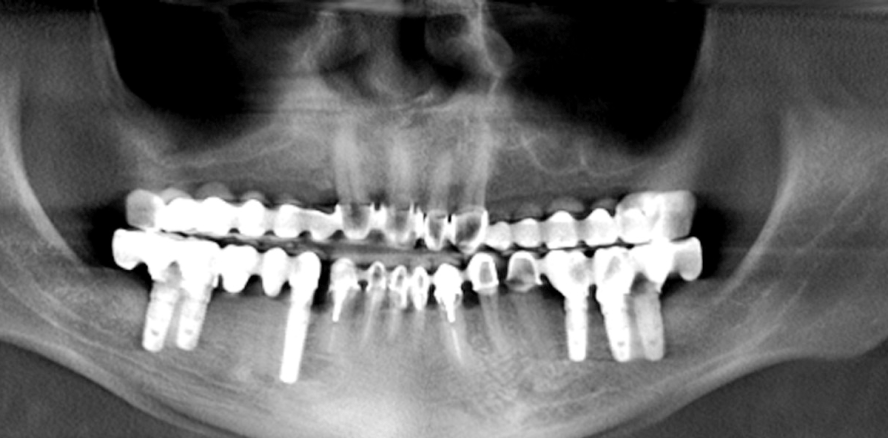

Wenn man nur die Panoramarekonstruktion aus DVT-Datensätzen (Abb. 1) in Betracht gezogen hätte, könnte man sofort anhand der angefertigten DVT-Aufnahme feststellen, dass es sich im Unterkiefer bei beiden Hybridbrücken in Regio 38 und 48 um Implantate und in Regio 39 und 49 um Brückenanhänger handelt. Selbstverständlich kann die distale Verlängerung der festsitzenden Brücken über die Hauptkauregion hinaus unter bestimmten Umständen empfehlenswert sein, aber diese überdimensionierte prothetische Versorgung scheint unrealistisch.

Zur effektiven Befundung empfiehlt es sich, zuerst alle axialen Schnitte der DVT-Aufnahme durchzugehen – dann wären die typischen Merkmale von Bewegungsartefakten der DVT-Aufnahme, wie z. B. Unschärfe, Streifenartefakte, mehr Rauschen im Bild sowie Mehrfachkonturen an Implantaten und Wurzelkanalfüllungen, sofort erkennbar gewesen (Abb. 2).1,2,4,6–8

Nach erneuter Aufklärung des Patienten wurde eine zweite DVT-Aufnahme erfolgreich angefertigt (Abb. 3). Diese machte deutlich, dass die Implantate in Regio 38 und 48 nur Doppelkonturen der Implantate 37 und 47 waren. Zahn 31 wurde noch nicht entfernt, Doppelkonturbildungen an Brückenanhänger, Zahnimplantat sowie der Lückenschluss Regio 31 waren nur die Folge einer Patientenbewegung während der ersten DVT-Anfertigung.